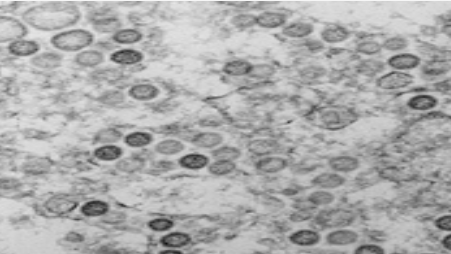

- ▲ ⓒ질병관리청